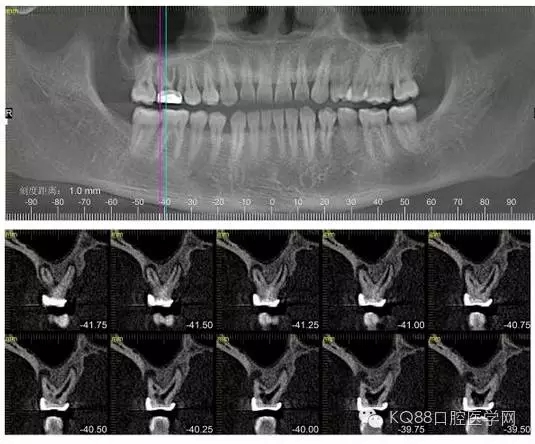

下面是拔牙前 CBCT

清晰可見(jiàn)根尖部陰影區(qū)域明顯。遠(yuǎn)中頰根

近中頰跟,同時(shí)可以看出離上頜竇比較近,且伴有骨缺損。

這個(gè)切面可以看到根裂。